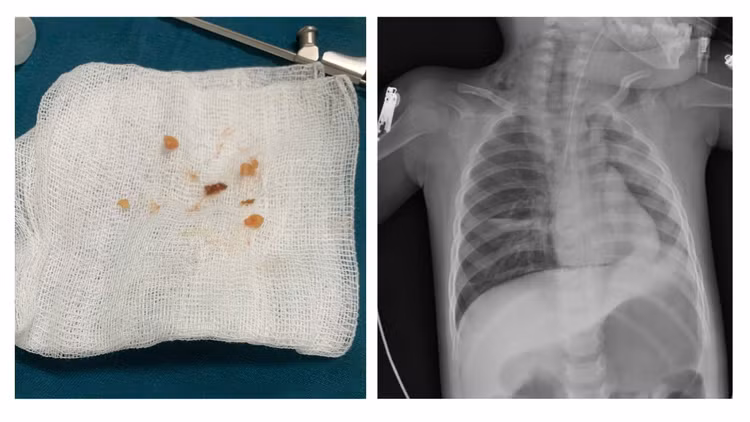

Thậm chí, đã có thời điểm trẻ ngừng tim. Các hình ảnh chụp X-Quang ngực cho thấy hai bên phổi của trẻ mờ rải rác, nhất là tại vùng đỉnh và cạnh rốn phổi, góc sườn hoành hai bên nhọn.